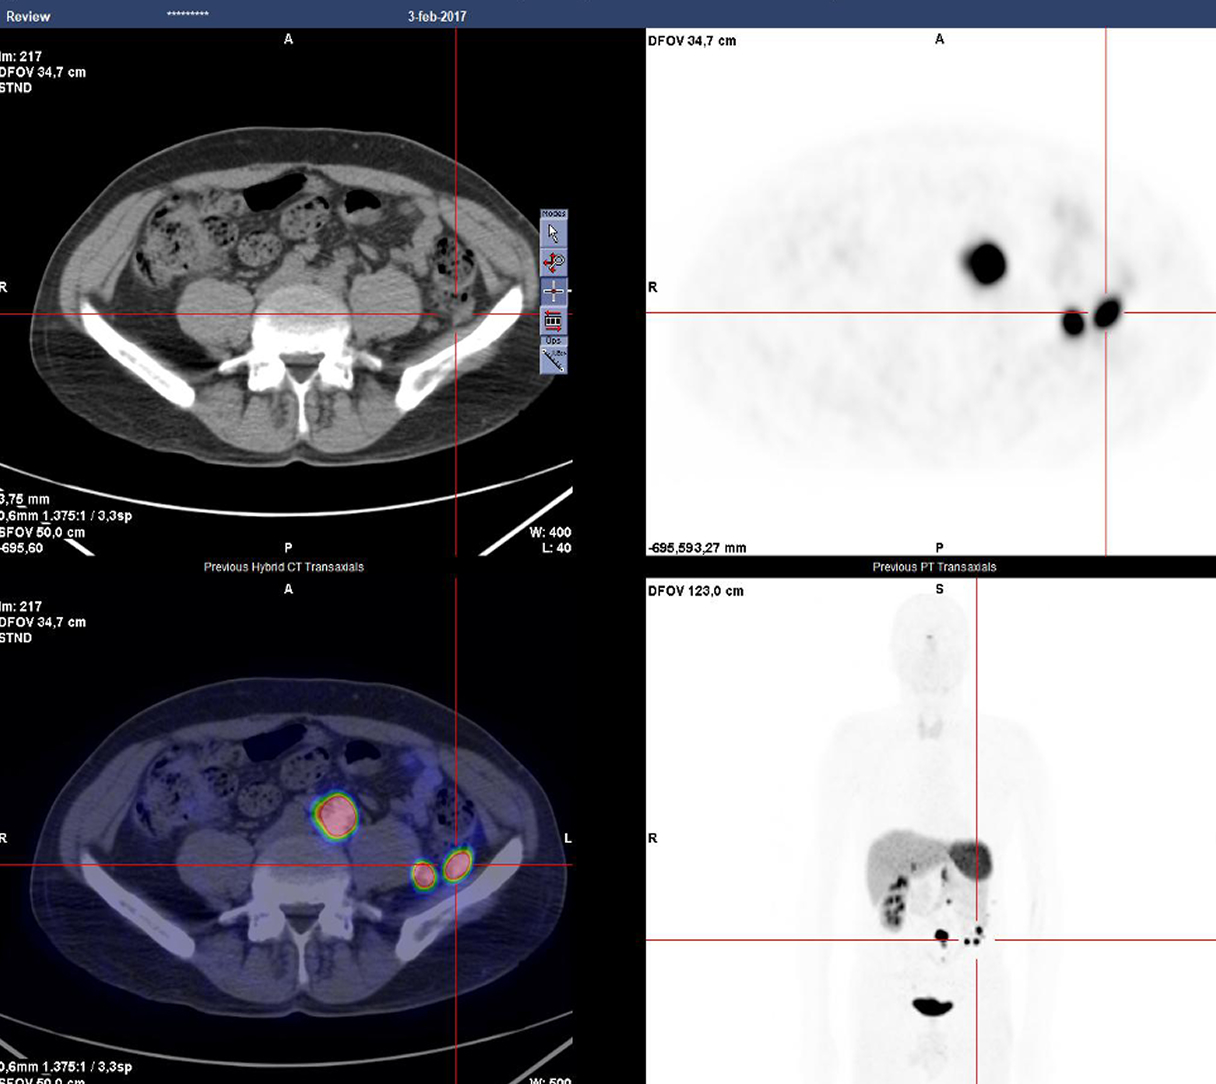

Caso condiviso da Saima Mushtaq

Paziente con anamnesi di malattia coronarica e pregresso impianto di stent sulla discendente anteriore sinistra.

Per prima cosa, esamina l'intera scansione. Concentrati sul tronco comune e sulla porzione prossimale della discendente anteriore sinistra.